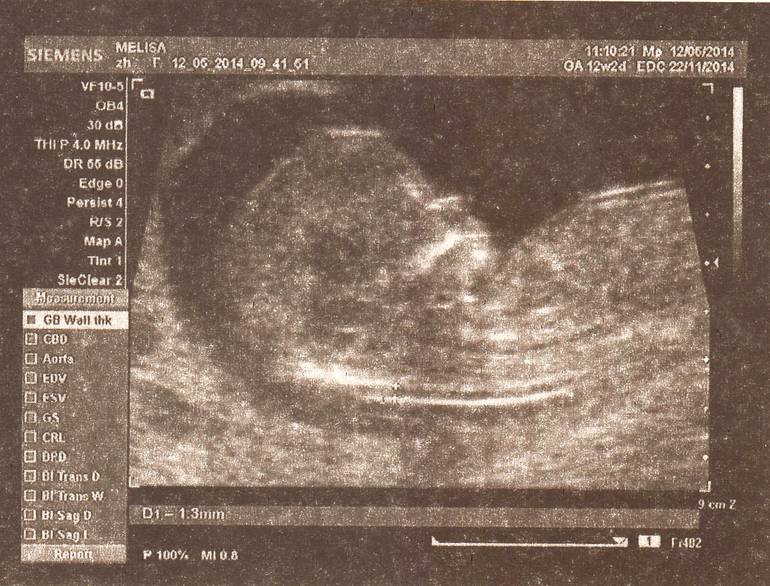

Были сегодня на УЗИ! У нас все отлично! Плод развивается хорошо, все соответствует срокам. Увидели все: ручки, ножки, носик, и даже позвоночник и сердечко. Мы с мужем на седьмом небе от счастья! Я уже люблю своего малыша. =)

КТР - 59 мм.

БПР - 21 мм.

ЧСС - 156 уд./мин.

Кости черепа и кости носа визуализируются. Фронтомаскилярный угол < 85*.

Воротниковое пространство - 1,3 мм.

Передняя брюшная стенка сформирована.

Хорион - 14 мм. Хорион расположен по задней стенке, не достигает области внутреннего зева, фиксирован на всем протяжении.

Количество околоплодных вод нормальное.

Длина шейки матки - 34 мм.

Желточный мешочек не визуализируется.

Заключение: беременность 12-13 нед. (фетометрически).